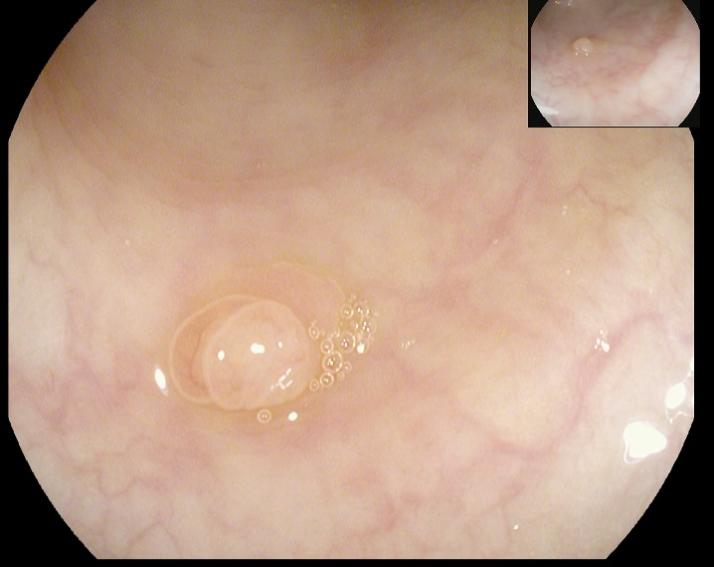

黄先生(32岁,升结肠息肉,图4)

肠镜一照,息肉现形!形态各异的大肠息肉,离癌有多远?(图4)

图4

病理诊断:潴留性息肉(或称幼年性息肉)。

解读:这类息肉常见于儿童和青少年,但成人也可发生。是黏膜腺体扩张、分泌物潴留形成的错构瘤性病变,本质上是良性,通常不具有癌变潜能。距离癌:基本安全,良性息肉。